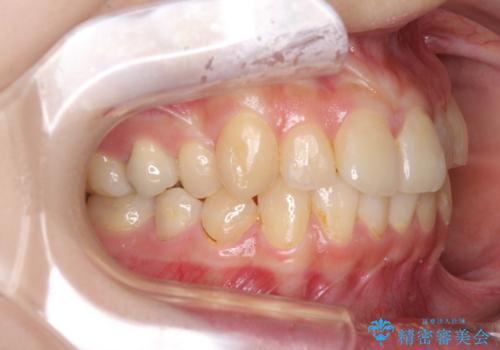

デコボコ歯列をきれいに インビザラインによる矯正治療

- 上下歯列全体のデコボコを気にして来院された患者様です。

主に下顎歯列全体の後方移動とIPR(歯と歯の間を削る)によってデコボコが解消するように設計し、インビザラインにより治療を行うこととしました。

奥歯の知覚過敏が顕著となり、その影響で奥歯の咬み合わせ改善のための顎間ゴムの装着ができず、咬合を仕上げるまでに長い期間を要することとなりました。